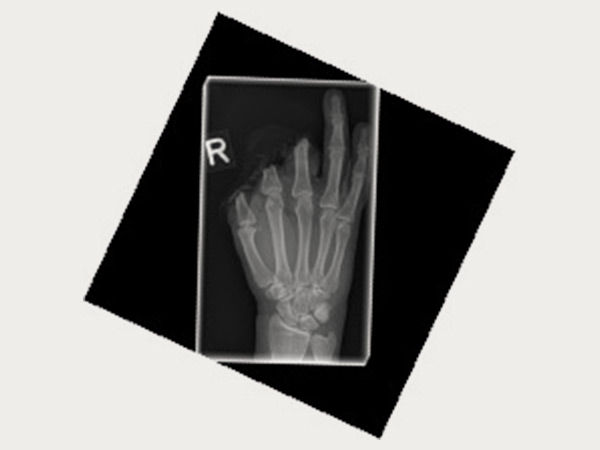

Wenn es zu einer komplexen Handverletzung kommen sollte, sind Sie an unserem standortübergreifenden Zentrum im Notfall rund um die Uhr bestens aufgehoben. Arbeits- und Wegeunfälle (Berufsgenossenschaft) werden schwerpunktmäßig behandelt. Dank der Zulassung als Schwerstverletzungsartenverfahren (SAV) Hand Trauma Zentrum durch die DGUV konnten wir bestmögliche Bedingungen zur chirurgischen Versorgung von schwersten Handverletzungen inklusive Fingeramputationen schaffen. Ein handchirurgisches Replantationsteam steht rund um die Uhr zur Verfügung.